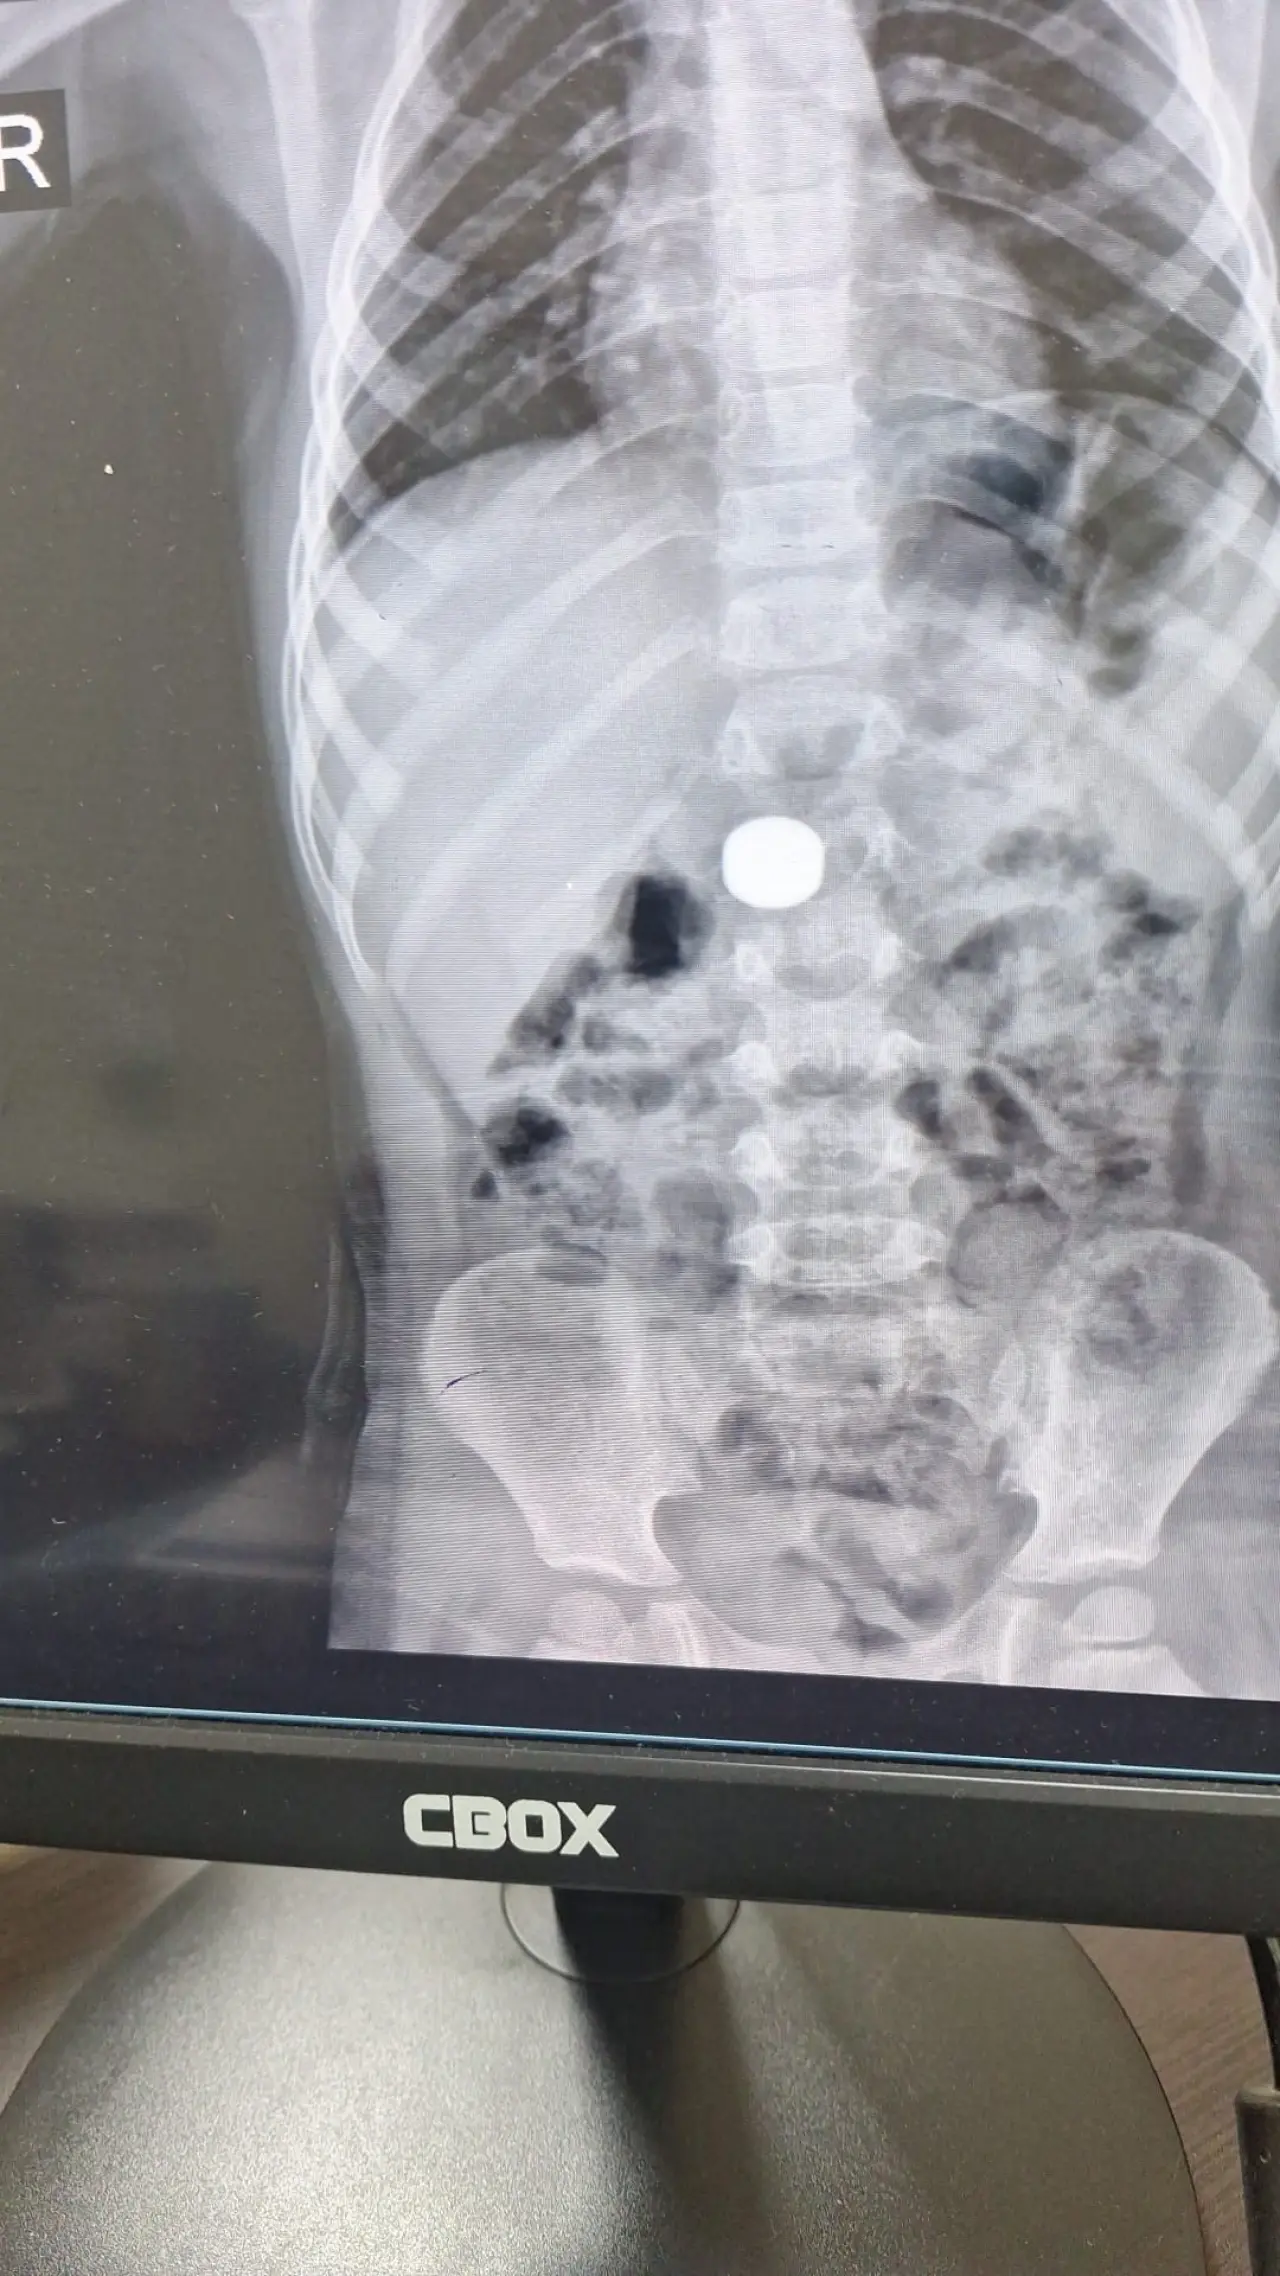

Ailesinin mıknatıs yuttuğundan şüphelenmesi üzerine Karaman Eğitim ve Araştırma Hastanesi Acil Servisi’ne götürülen İ.K.’nin yapılan tetkiklerinde, ince bağırsağında iki adet mıknatıs bulunduğu tespit edildi. Çocuk, 5 gün boyunca gözlem altında tutuldu.

Çocuk Cerrahisi Uzmanı Doç. Dr. Mehmet Uysal, takip sürecinde çekilen görüntülerde mıknatısların yer değiştirmediğini belirterek, “Hastayı genel anestezi altında ameliyata aldık. İnce bağırsakta iki mıknatısın birbirine yapışık halde olduğunu gördük. Gerçekleştirdiğimiz operasyonla mıknatısları çıkardık. Ameliyat sonrası hastamız üçüncü gününde taburcu edildi, genel durumu iyi” dedi.